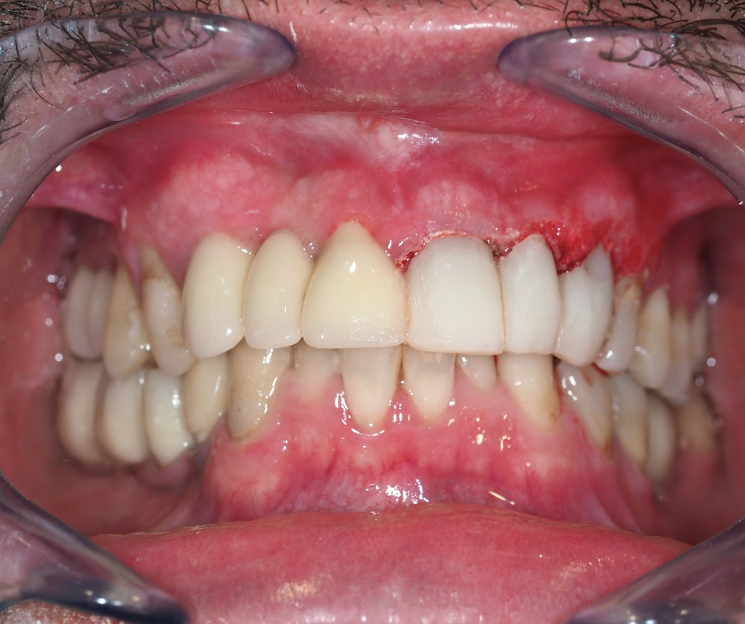

Paciente con infecciones de origen dental que comprometían severamente el hueso alveolar en la zona anterior superior. Se realizó la extracción de los dientes 21, 22 y 23, y se optó por una rehabilitación inmediata mediante implantes córticobasales.

Esta combinación permitió anclar los implantes en hueso cortical, que mantiene su estabilidad incluso en presencia de procesos infecciosos en el hueso alveolar. El resultado: rehabilitación funcional y estética el mismo día de la cirugía.

La rehabilitación postextracción de los dientes 21, 22 y 23 con implantes córticobasales no es un caso aislado. Es un ejemplo claro de cómo la odontología moderna puede resolver situaciones complejas de forma inmediata, estética y funcional.